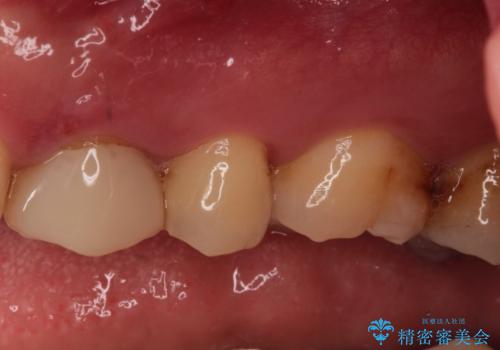

- 定期健診にて虫歯が見つかった患者さんです。他院で保険治療(CR、プラスチック)したところとまだ処置されていないところが虫歯になっていました。

セラミックインレーで治療しました。

以前保険治療で治したところが再び虫歯になっていました。保険治療で使用される材料は主にプラスチックなので必ず劣化がおきます。再治療のリスクを減らすために、セラッミックインレーで治療を行いました。セラミックインレーには劣化がほとんどありません。当院ではシリコンで型取りを行っているので、適合が良い被せものが出来き再治療のリスクを減らすことが出来ます。